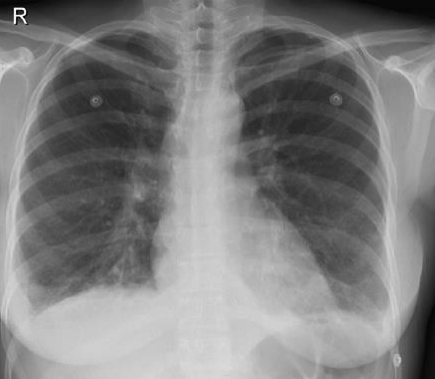

Leia o caso a seguir para responder às questões de 22 a 24.

Paciente 68 anos de idade, do sexo masculino, refere dispneia progressiva há 2 anos, inicialmente aos grandes esforços e atualmente aos pequenos esforços, associado com tosse seca frequente. Nega outros sintomas associados.

Ex-tabagista de 10 maços-ano, cessou o hábito há 20 anos.

Criou 2 pássaros em gaiola, em casa por 2 anos, cessou há 15 anos.

Trabalha em escritório de advocacia por toda a vida. Nega contato com mofo. Nega uso de medicações contínuas prévias ou atuais.

Ao exame em bom estado geral, leve dispneia, baqueteamento digital, IMC: 20, FR: 24irm, FC: 90 bpm, PA: 120x80mmHg, spO2 90% em ar ambiente. Ausculta pulmonar: estertores finos em velcro bibasais. Sem outras alterações.

Traz resultado de exame:

FAN negativo, FATOR REUMATÓIDE negativo

Espirometria: distúrbio ventilatório restrivo acentuado.

Tomografia de tórax: padrão típico de PIU (pneumopatia intersticial usual).

Enunciado 3206467-1

Qual é o tratamento indicado para esse paciente?

Enunciado 3206466-1

Qual é a melhor conduta para confirmar o diagnóstico desse paciente?

Enunciado 3206465-1

Qual é o diagnóstico mais provável para o paciente?